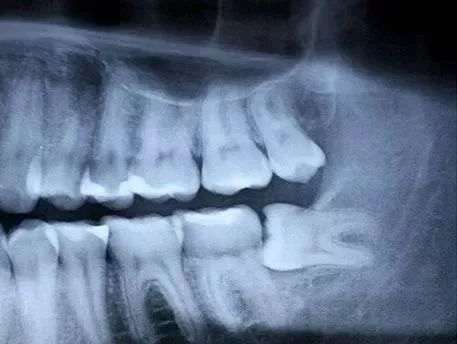

智齿刚萌出时的牙周膜时牙周膜对智齿“抓”得还没那么牢固,再加上周围骨质较松,拔牙时骨阻力较少。欣赏一下整齐的、牙根尚未发育完全的智齿↓

医生拔得轻松,你也恢复得更快。18岁的牙根 vs 28岁的牙根↓